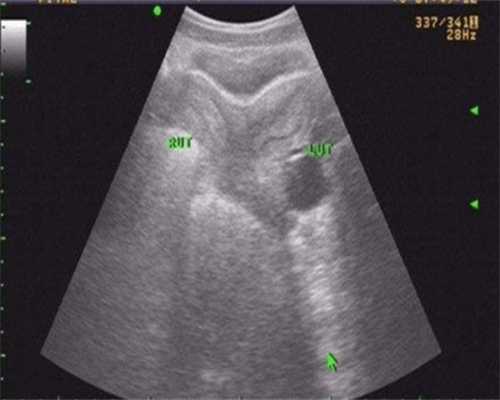

2.胚胎冷冻移植前女性需要憋尿,胚胎学家需要选择适合胚胎发育的地方进行移植。然后放入专用的试管,在超声的引导下,配合临床医生通过宫颈管将胚胎注入宫腔。